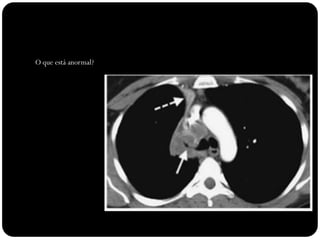

O que está anormal?

Atelectasia LSD

Sinal do S de Golden

Causado por

carcinoma

broncogênico

Note deslocamento

da fissura menor,

elevação da cúpula

diafragmática

direita...